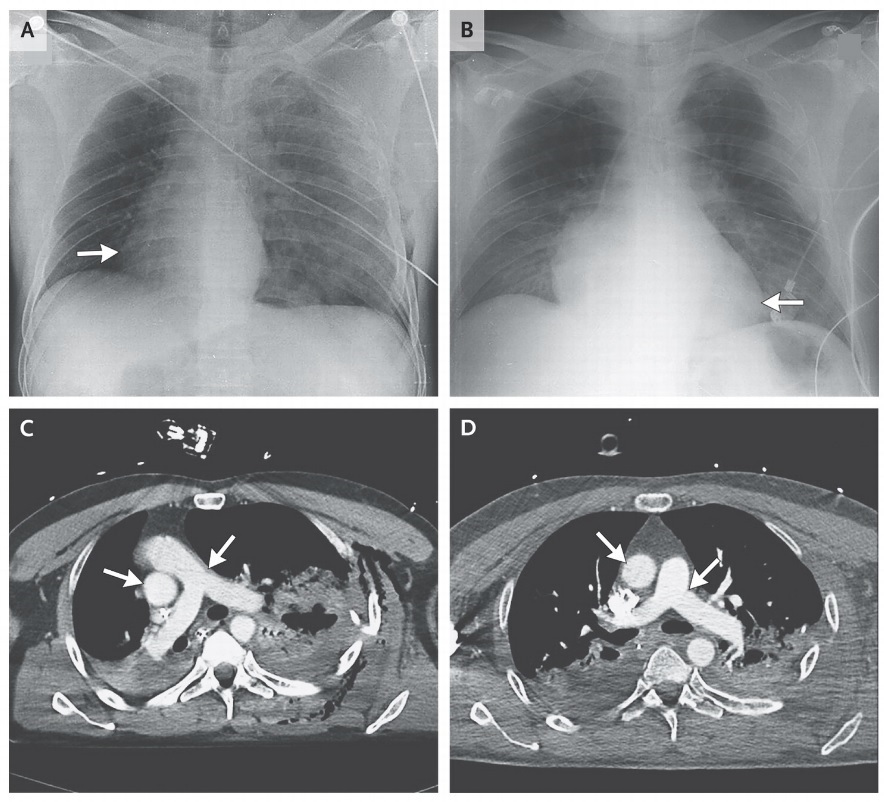

Totul a început în momentul în care bărbatul de 48 de ani, implicat într-un accident de motocicletă, a ajuns la spital, iar medicii nu au reuşit să-i audă bătăile inimii, deşi pacientul era conştient şi putea să comunice. Radiografia a arătat ce se întâmplase de fapt.

Medicii au fost uimiţi că bărbatul a supravieţuit unui asemenea traumatism. Ei au descoperit apoi că inima nu se rotise în momentul accidentului, ci la aproximativ o oră după aceea.

În urma şocului, din plămânii pacientului a început să iasă aer, care s-a acumulat în piept, aceste pungi cu aer ducând la mutarea inimii spre dreapta, explică Fontana.

După ce aerul a fost scos din torace, inima s-a deplasat la loc, iar după doar 24 de ore se afla în poziţia normală.